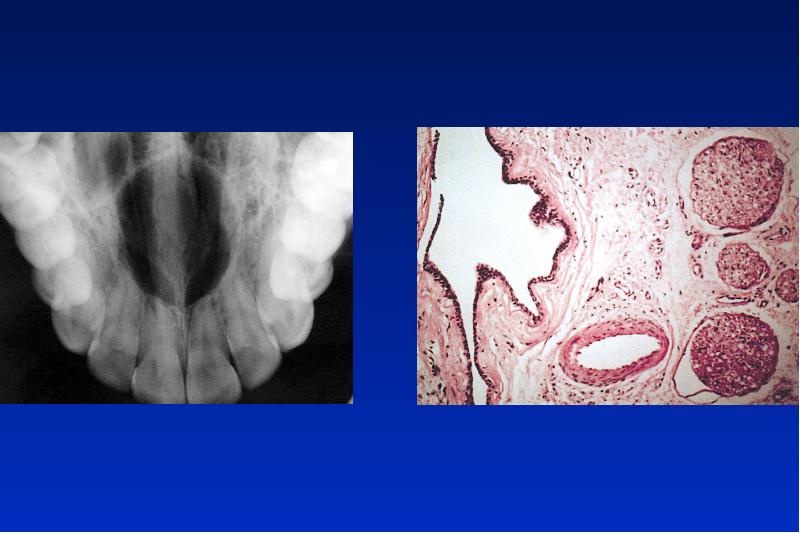

- 27. Nasopalatinale Zyste Ät: dysontogenetische Zyste Lok: OK Incisivusregion Alter: 40 -